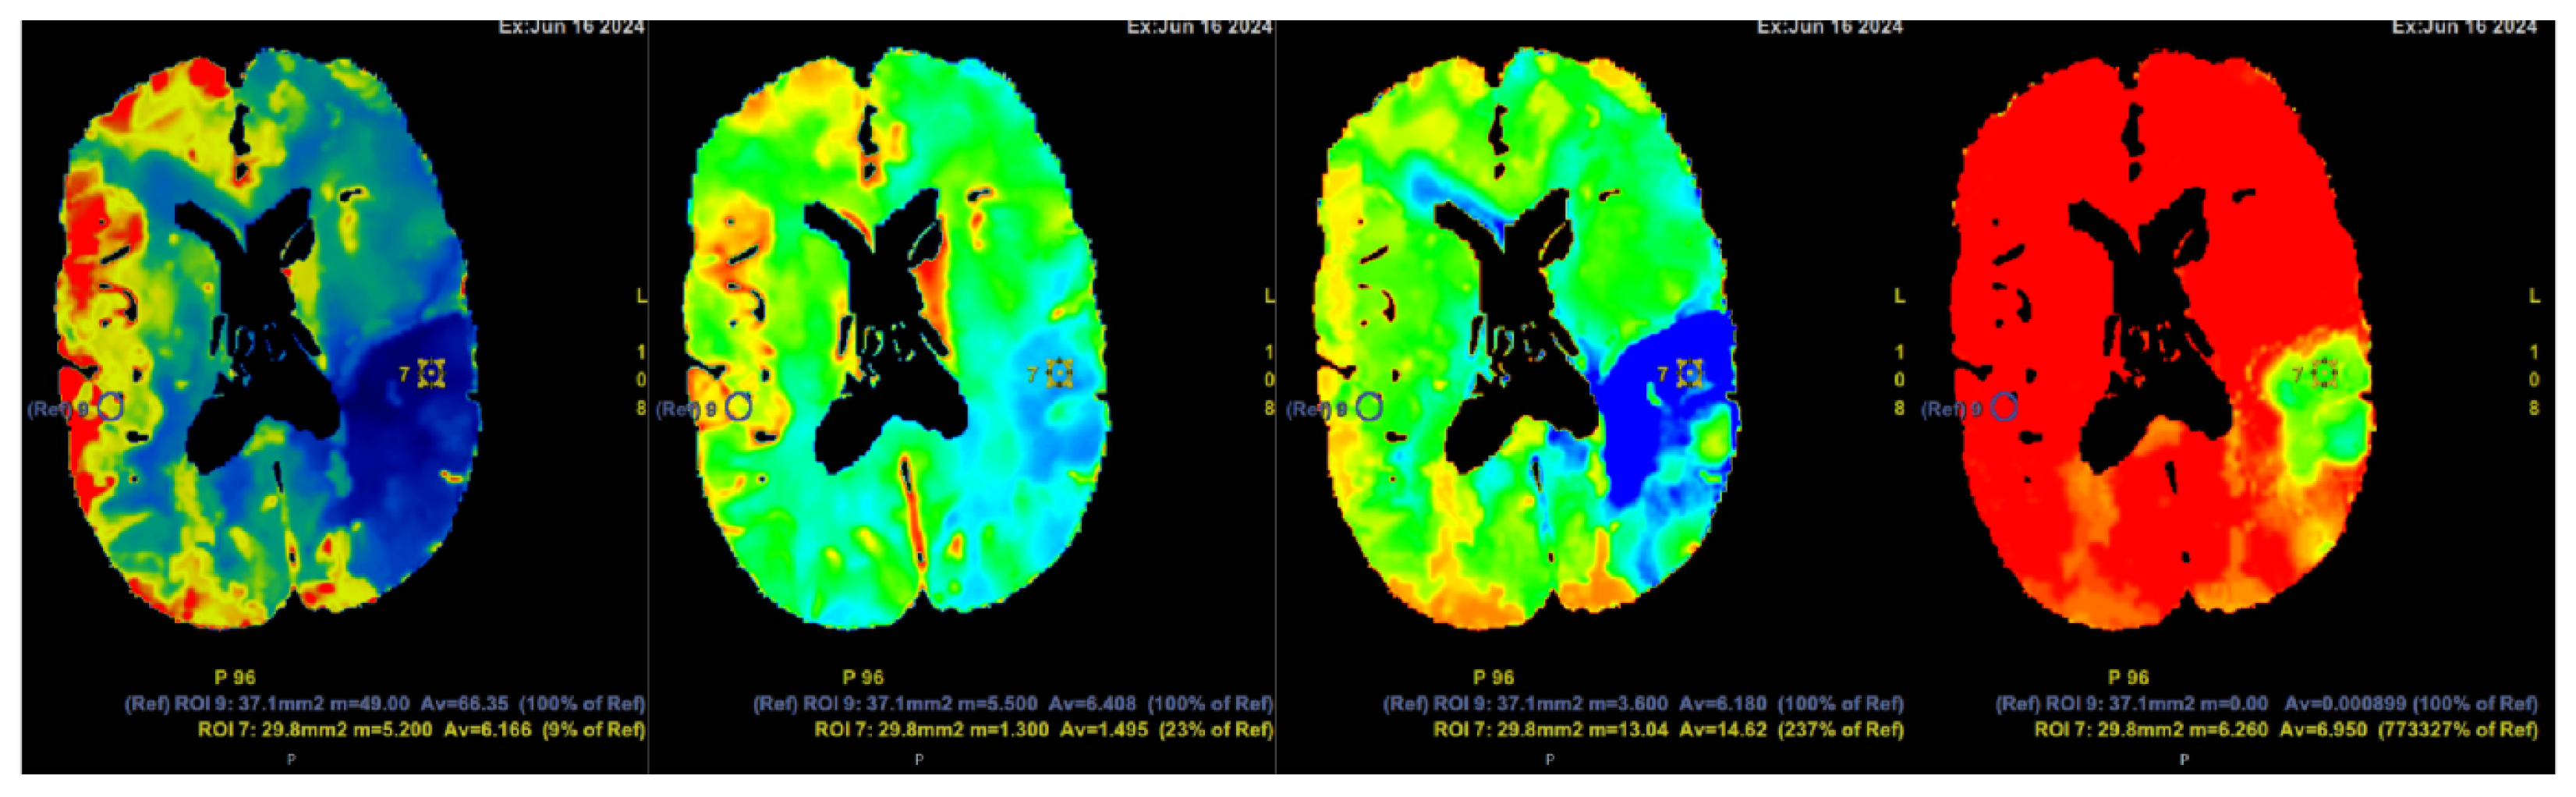

2. Case Presentation